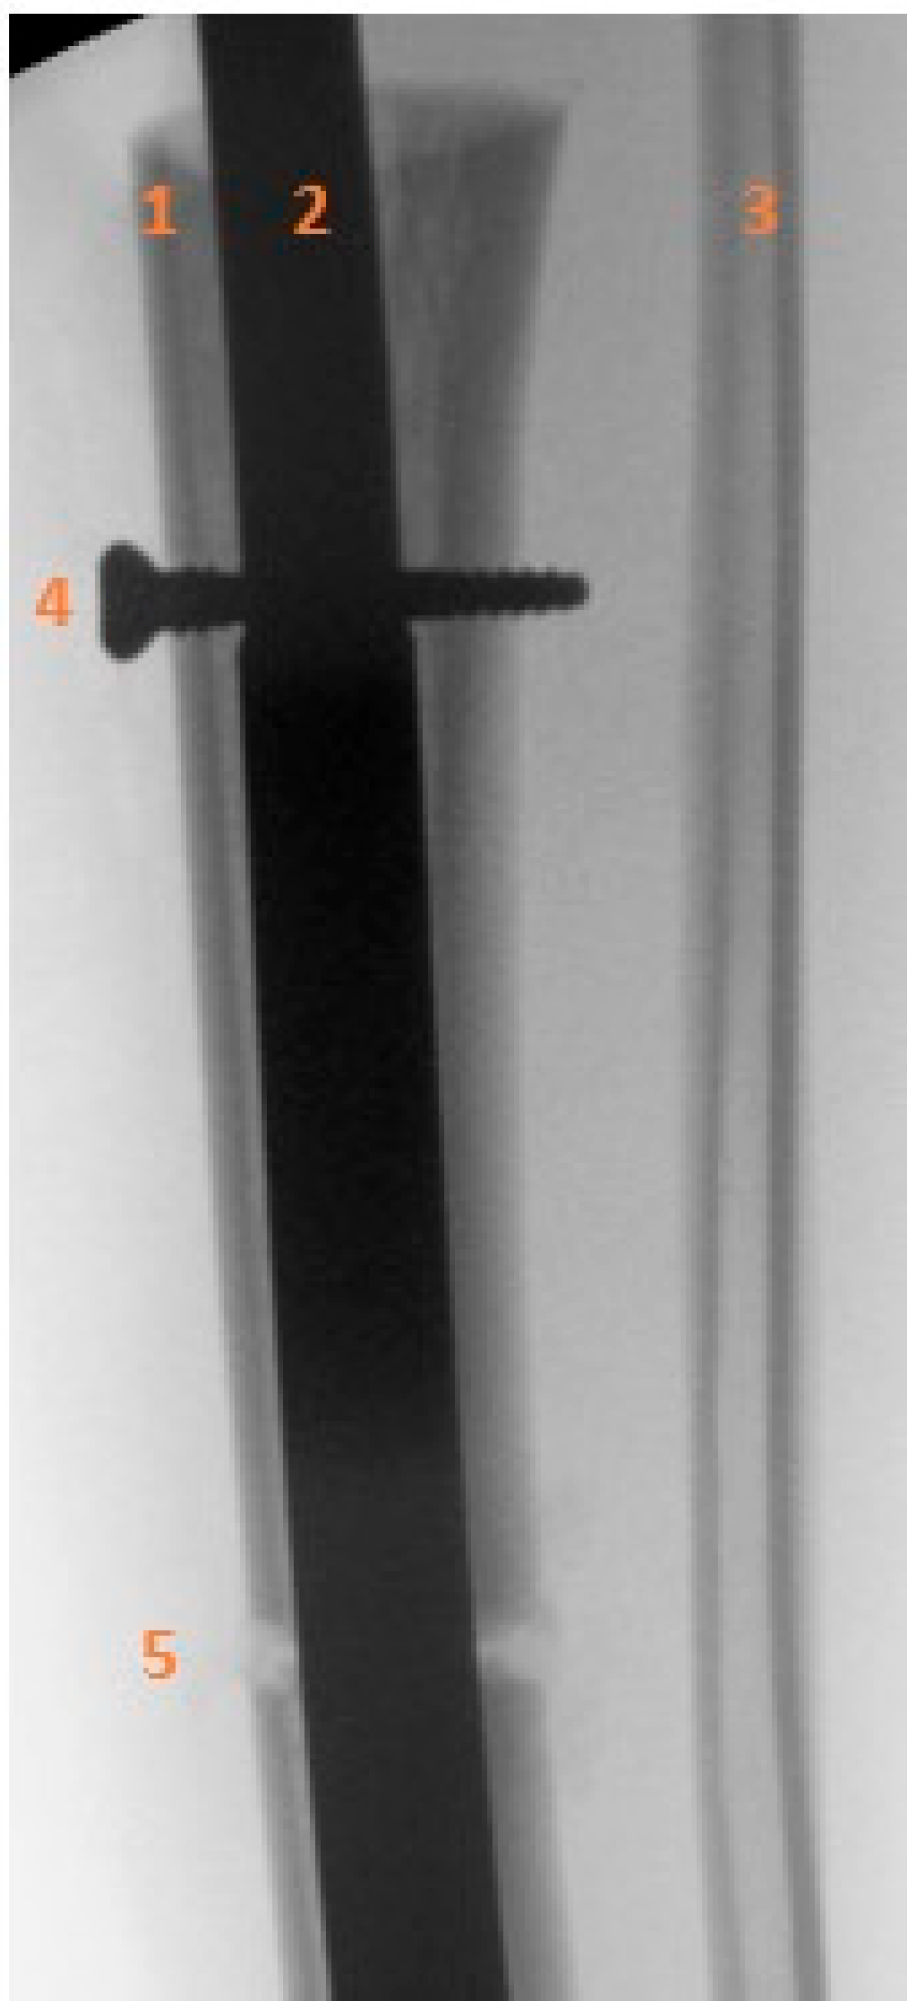

Figure 6.

Sequential anteroposterior radiographs following retrograde tibial bone transport at direct postoperative, 5 weeks, 4 months, 8 months, and 1.5 years. The initial segmental defect measured 9 cm. Remaining defect measured 8.5 cm at 5 weeks, 7 cm at 4 months, 1.5 cm at 8 months, and fully consolidated at 1.5 years. Progressive transport and callus formation are evident, with complete restoration of tibial length and alignment at 1.5 years. Distances are approximate due to image scaling.